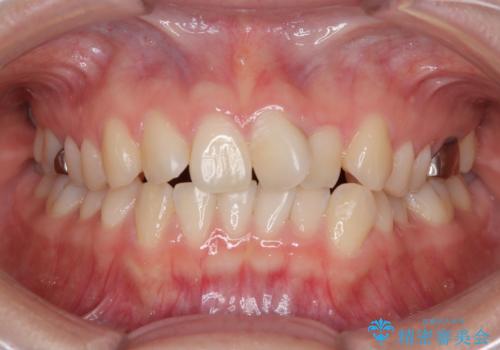

今回ご紹介するのは、「前歯のガタガタ(叢生)」と「奥歯のかみ合わせ(シザーズバイト)」にお悩みでご来院された患者様の症例です。

・上顎左右の第二大臼歯が頬側へ転移し、シザーズバイト(scissors bite)の状態

・上顎左側第二小臼歯が90度捻転しており、噛み合わせに影響

**前歯のデコボコ(叢生)**が整い、歯列全体が美しく改善

患者様にも「大人になってから矯正を始めることに不安もありましたが、思っていたよりも短期間で治療が終わって本当にうれしいです。前歯のガタガタも気にならなくなり、笑うことに自信が持てるようになりました!」と喜んでいただけました。